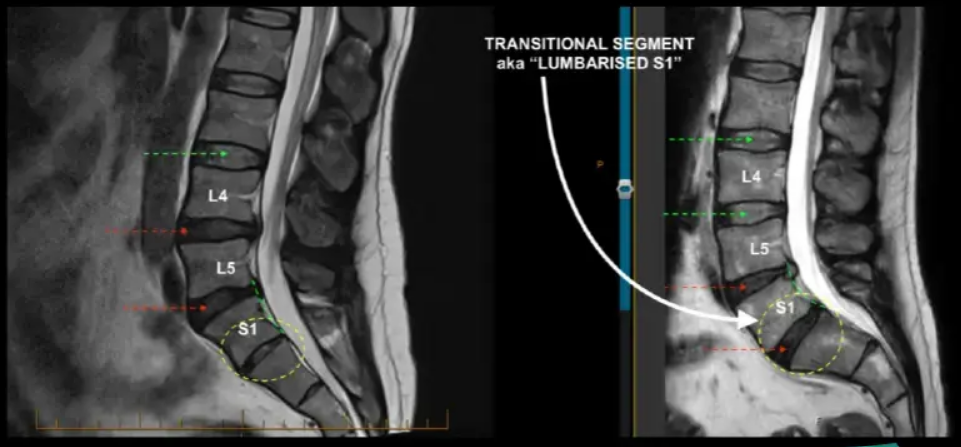

Lumbarization

Sacralization